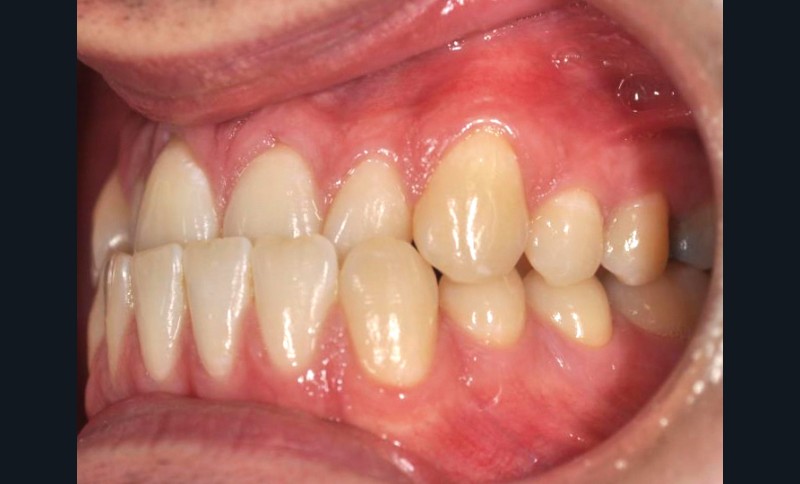

En intra-arcades (fig. 4-6), on note une classe III molaire et canine (fig. 4-5), trois plans d’occlusion, une déviation des milieux d’origine mandibulaire et un inversé articulé du bloc incisif maxillaire ; le biotype parodontal est fin, et l’on note des récessions gingivales (12, 13, 23, 33, 43) certainement dues à la mauvaise position et aux forces mal réparties lors de la mastication (fig. 5). L’arcade maxillaire est carrée avec une DDM antérieure (fig. 7), l’arcade mandibulaire étroite et allongée (fig. 8).